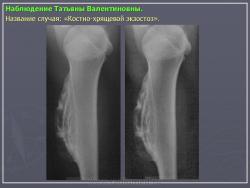

Наблюдения коллег.